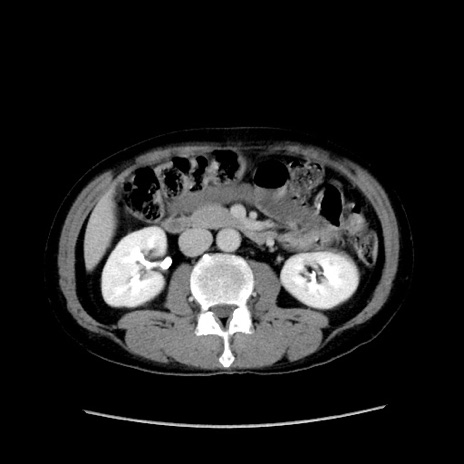

症例37(横断像)

【症例】40歳代 男性

【主訴】腹痛

【現病歴】4時間ほど前に電車に乗車中に臍部上より腹痛出現。徐々に増悪し起立困難となり、救急外来受診。生ものは数日食べていない。今朝お雑煮を食べた。

【身体所見】BT 36.8℃、BP 117/84mmHg、HR 91/min、SpO2 97%、苦悶様、腹部:臍上部広範囲圧痛あり、反跳痛±

【データ】WBC 8100、CRP 0.03